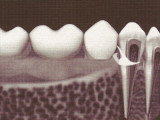

Sans racine, comme on le voit à la radio, vos prothèses restent mobiles, c'est à dire que vous pouvez les retirer de votre bouche même si leur stabilité est assurée quand vous souriez ou mastiquez.